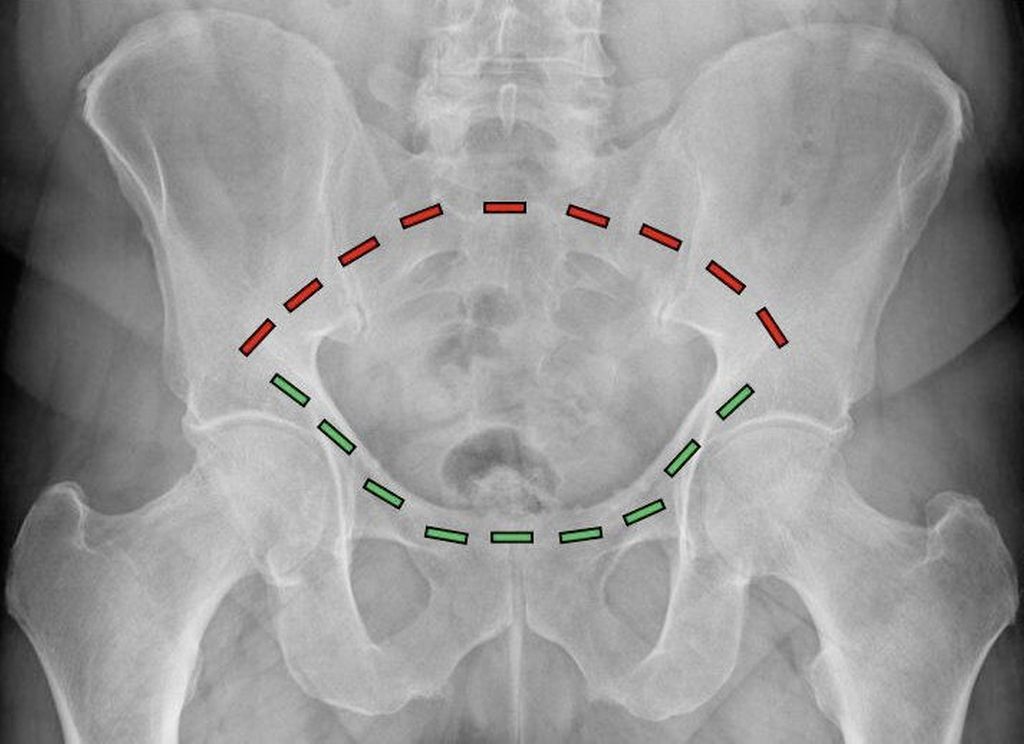

Abb. 1: Der Beckenring besteht aus einem vorderen (grüne Striche) und einem hinteren (rote Striche) Anteil. Während der vordere Beckenring durch die Schambeine gebildet wird, besteht der hintere Beckenring aus dem Kreuzbein und den Darmbeinen

FFP-Frakturen des geriatrischen Patienten entstehen im Gegensatz zu Beckenfrakturen des adulten Patienten als Folge eines niedrigenergetischen Traumas. Aufgrund der reduzierten Knochenqualität reichen also geringe Energiemengen aus, um das osteoporotisch veränderte Becken zu brechen. Für das Verständnis der Architektur des Beckens ist es entscheidend zu wissen, dass das Becken aus einer zusammengesetzten Ringkonstruktion besteht, wobei ein vorderer und ein hinterer Beckenring unterschieden werden (Abb. 1). Aufgrund des Kraftflusses, der aus dem Bein hauptsächlich über den hinteren Beckenring in den Rumpf verteilt wird, ist der hintere Beckenring für die Gesamtstabilität des knöchernen Beckens von primärer Bedeutung. Die FFP-Klassifikation gibt hier anhand der Beteiligung der unterschiedlichen Anteile des Beckenringes den gegenwärtig vollständigsten Überblick.1 In Abhängigkeit davon, ob es sich um ein- oder beidseitige Verletzungen des vorderen, des hinteren oder beider Beckenringe handelt, unterteilt diese Klassifikation in aufsteigendem Schweregrad die Verletzungsausprägung. Der Fokus der Behandlung der FFP-Frakturen liegt ebenso wie auch bei der Behandlung der Beckenverletzungen des Erwachsenen auf der Stabilisierung des hinteren Beckenringes. Im Gegensatz zu den Beckenringfrakturen des Erwachsenen, deren Entstehung eine hohe Verletzungsenergie und damit verbundene, lebensbedrohliche Begleitverletzungen wie Blutungen beinhalten, stehen bei den FFP-Frakturen aufgrund der niedrigen Verletzungsenergie die Schmerzbehandlung und die zügige Mobilisierung des Patienten im Vordergrund. Als ursächliche Mechanismen der Entstehung einer FFP-Verletzung gelten Stürze im häuslichen Umfeld bei geringer Fallhöhe und niedriger Aufprallenergie.